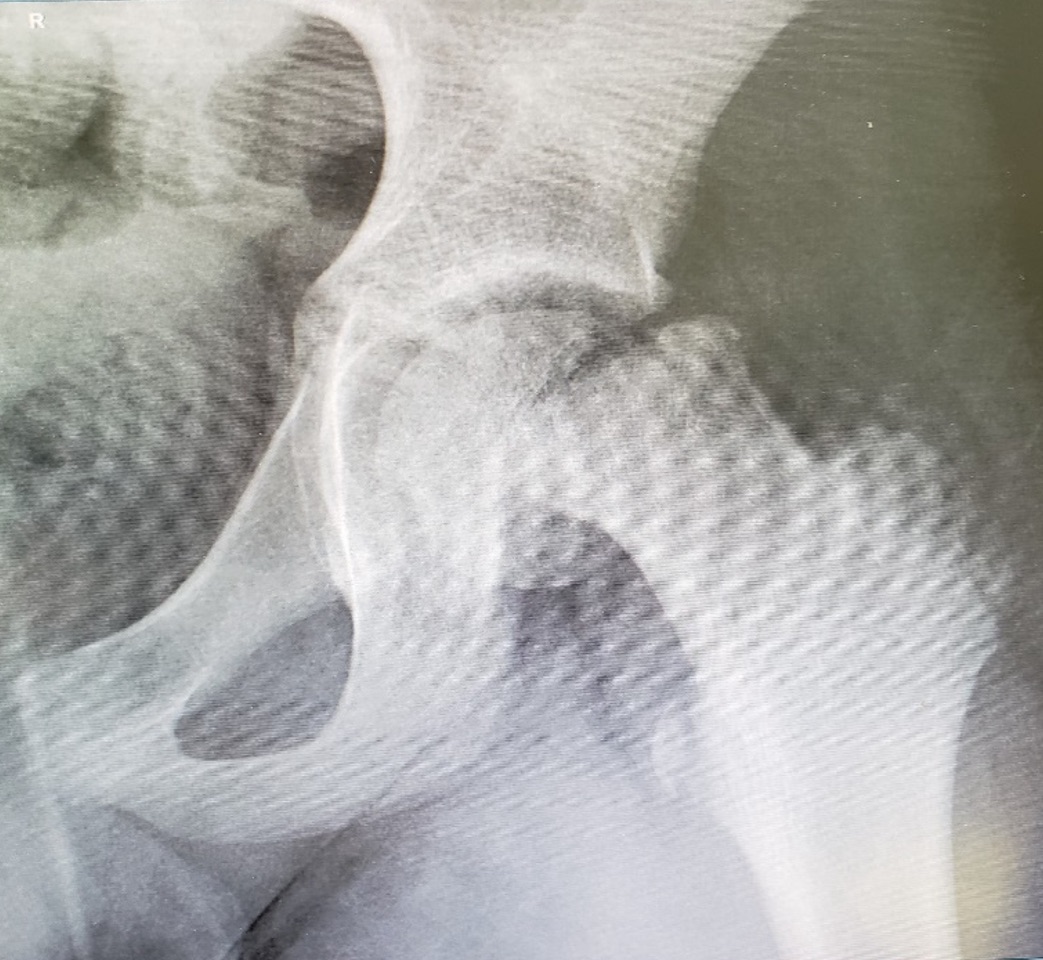

What is slipped capital femoral epiphysis?

it is when the femoral head slips off neck of femur

happens more in the adolescent and growth spurt years

What are the signs and symptoms of slipped capital femoral epiphysis?

hip pain that radiates to the groin or thigh

limping

stiffness

loss of motion

can't bear weight on the affected side

What is the medical management of slipped capital femoral epiphysis?

x ray to confirm dx

non weight bearing to prevent further injury

surgery within 24 hrs